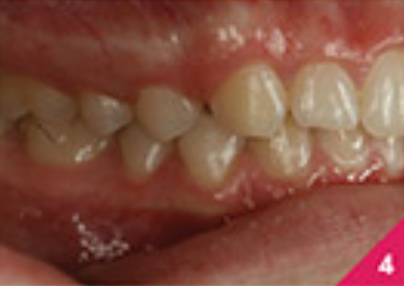

Процес лікування складається із шести фаз, із загальною кількістю 24 елайнери та тривалістю лікування — 16 місяців. Під час лікування, лікар відмітила, що пацієнтка була винятково мотивованою та підтримувала відмінну гігієну ротової порожнини протягом періоду лікування. Для ретенції було застосовано елайнери, ідентичні до тих, які були використані на фінальному етапі лікування 6D елайнерів. На передніх зубах верхньої щелепи були зроблені мінімальні реставрації реконтурування емалі з метою покращення естетичного вигляду.

Лікування показало хороші результати, які можна побачити на фото з 6 по 10. Лікар відмітила, що протягом процесу лікування з'явилася незначна рецесія ясен на правому центральному різці нижньої щелепи. Пацієнтку було скеровано на консультацію до пародонтолога та, можливо, трансплантацію ясен.